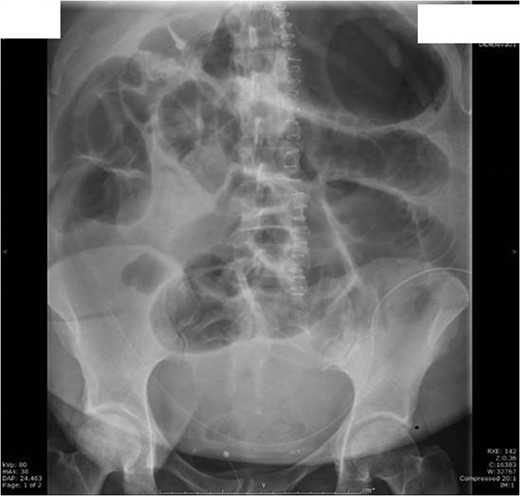

Unfortunately post laparotomy she developed ileus (Fig. 4) and laparotomy wound dehiscence. Finally 13 days post laparotomy she was discharged home with district nursing for wound management and stoma care.

Day 3 post laparotomy she developed ileus with significant gaseous distension involving the large and small bowel; with multiple air-fluid levels on horizontal beam imaging.